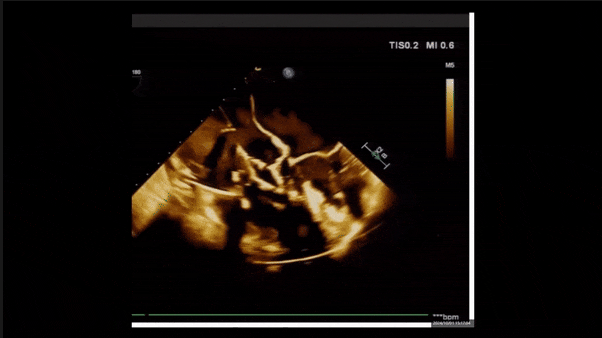

術(shù)前TEE評估

1、3D TEE顯示雙房及右室擴(kuò)大,右室中段直徑40mm,右室FCA 52%。三尖瓣環(huán)TAPSE 22mm,三尖瓣環(huán)左右徑49mm,三尖瓣隔葉長度16mm,前葉長度21mm,后葉長度34mm,三尖瓣前隔gap 11mm,后隔gap 5.6mm,AP gap 12mm,診斷極重度功能性三尖瓣返流(Type I型三尖瓣:Torrential FTR 5+)。

2、彩色多普勒顯示:收縮期三尖瓣口返流束起源于后隔交界、前后葉之間及前隔交界,返流束縮流頸最大寬度27mm,三尖瓣返流口EOA=2.02cm2,返流容積124ml,收縮期三尖瓣返流峰值速度2.64m/s,返流峰值壓差28mmHg,PAPs 43mmHg,舒張期三尖瓣口平均跨瓣壓差1mmHg,肝左靜脈可見明顯逆向血流波。